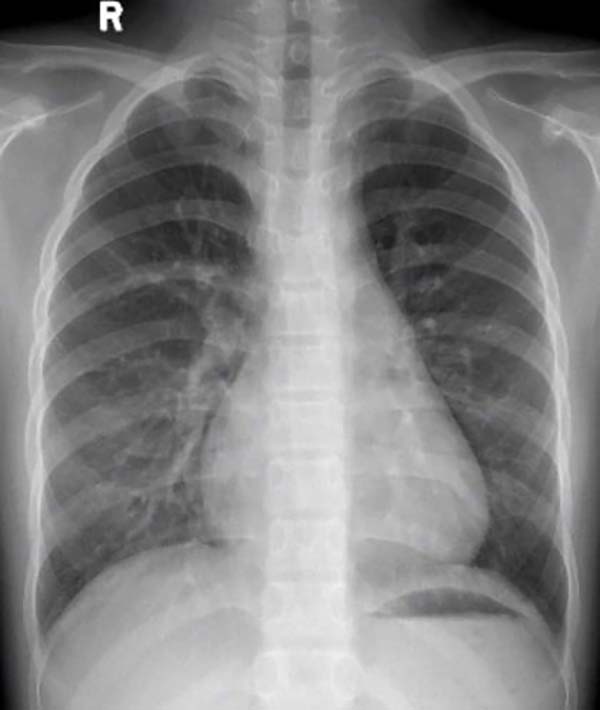

封堵器植入后胸片,无任何异物显影